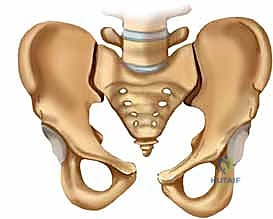

لفهم أهمية التثبيت الخارجي للحوض، يجب أولاً أن نفهم البنية التشريحية المذهلة لهذه المنطقة من الجسم. الحوض ليس عظمة واحدة، بل هو حلقة عظمية قوية تتكون من عدة أجزاء مترابطة بإحكام شديد بواسطة أربطة هي من أقوى الأربطة في جسم الإنسان.

يتكون الحوض بشكل رئيسي من:

* العجز (Sacrum): وهو عظمة مثلثة الشكل تقع في قاعدة العمود الفقري وتشكل الجزء الخلفي من حلقة الحوض.

* العصعص (Coccyx): عظمة صغيرة في نهاية العجز.

* العظمتان اللامسماتان (Innominate bones): وتتكون كل منهما من التحام ثلاث عظام هي: الحرقفة (Ilium)، الإسك (Ischium)، والعانة (Pubis). تلتقي هذه العظام في الأمام عند الارتفاق العاني (Symphysis pubis).